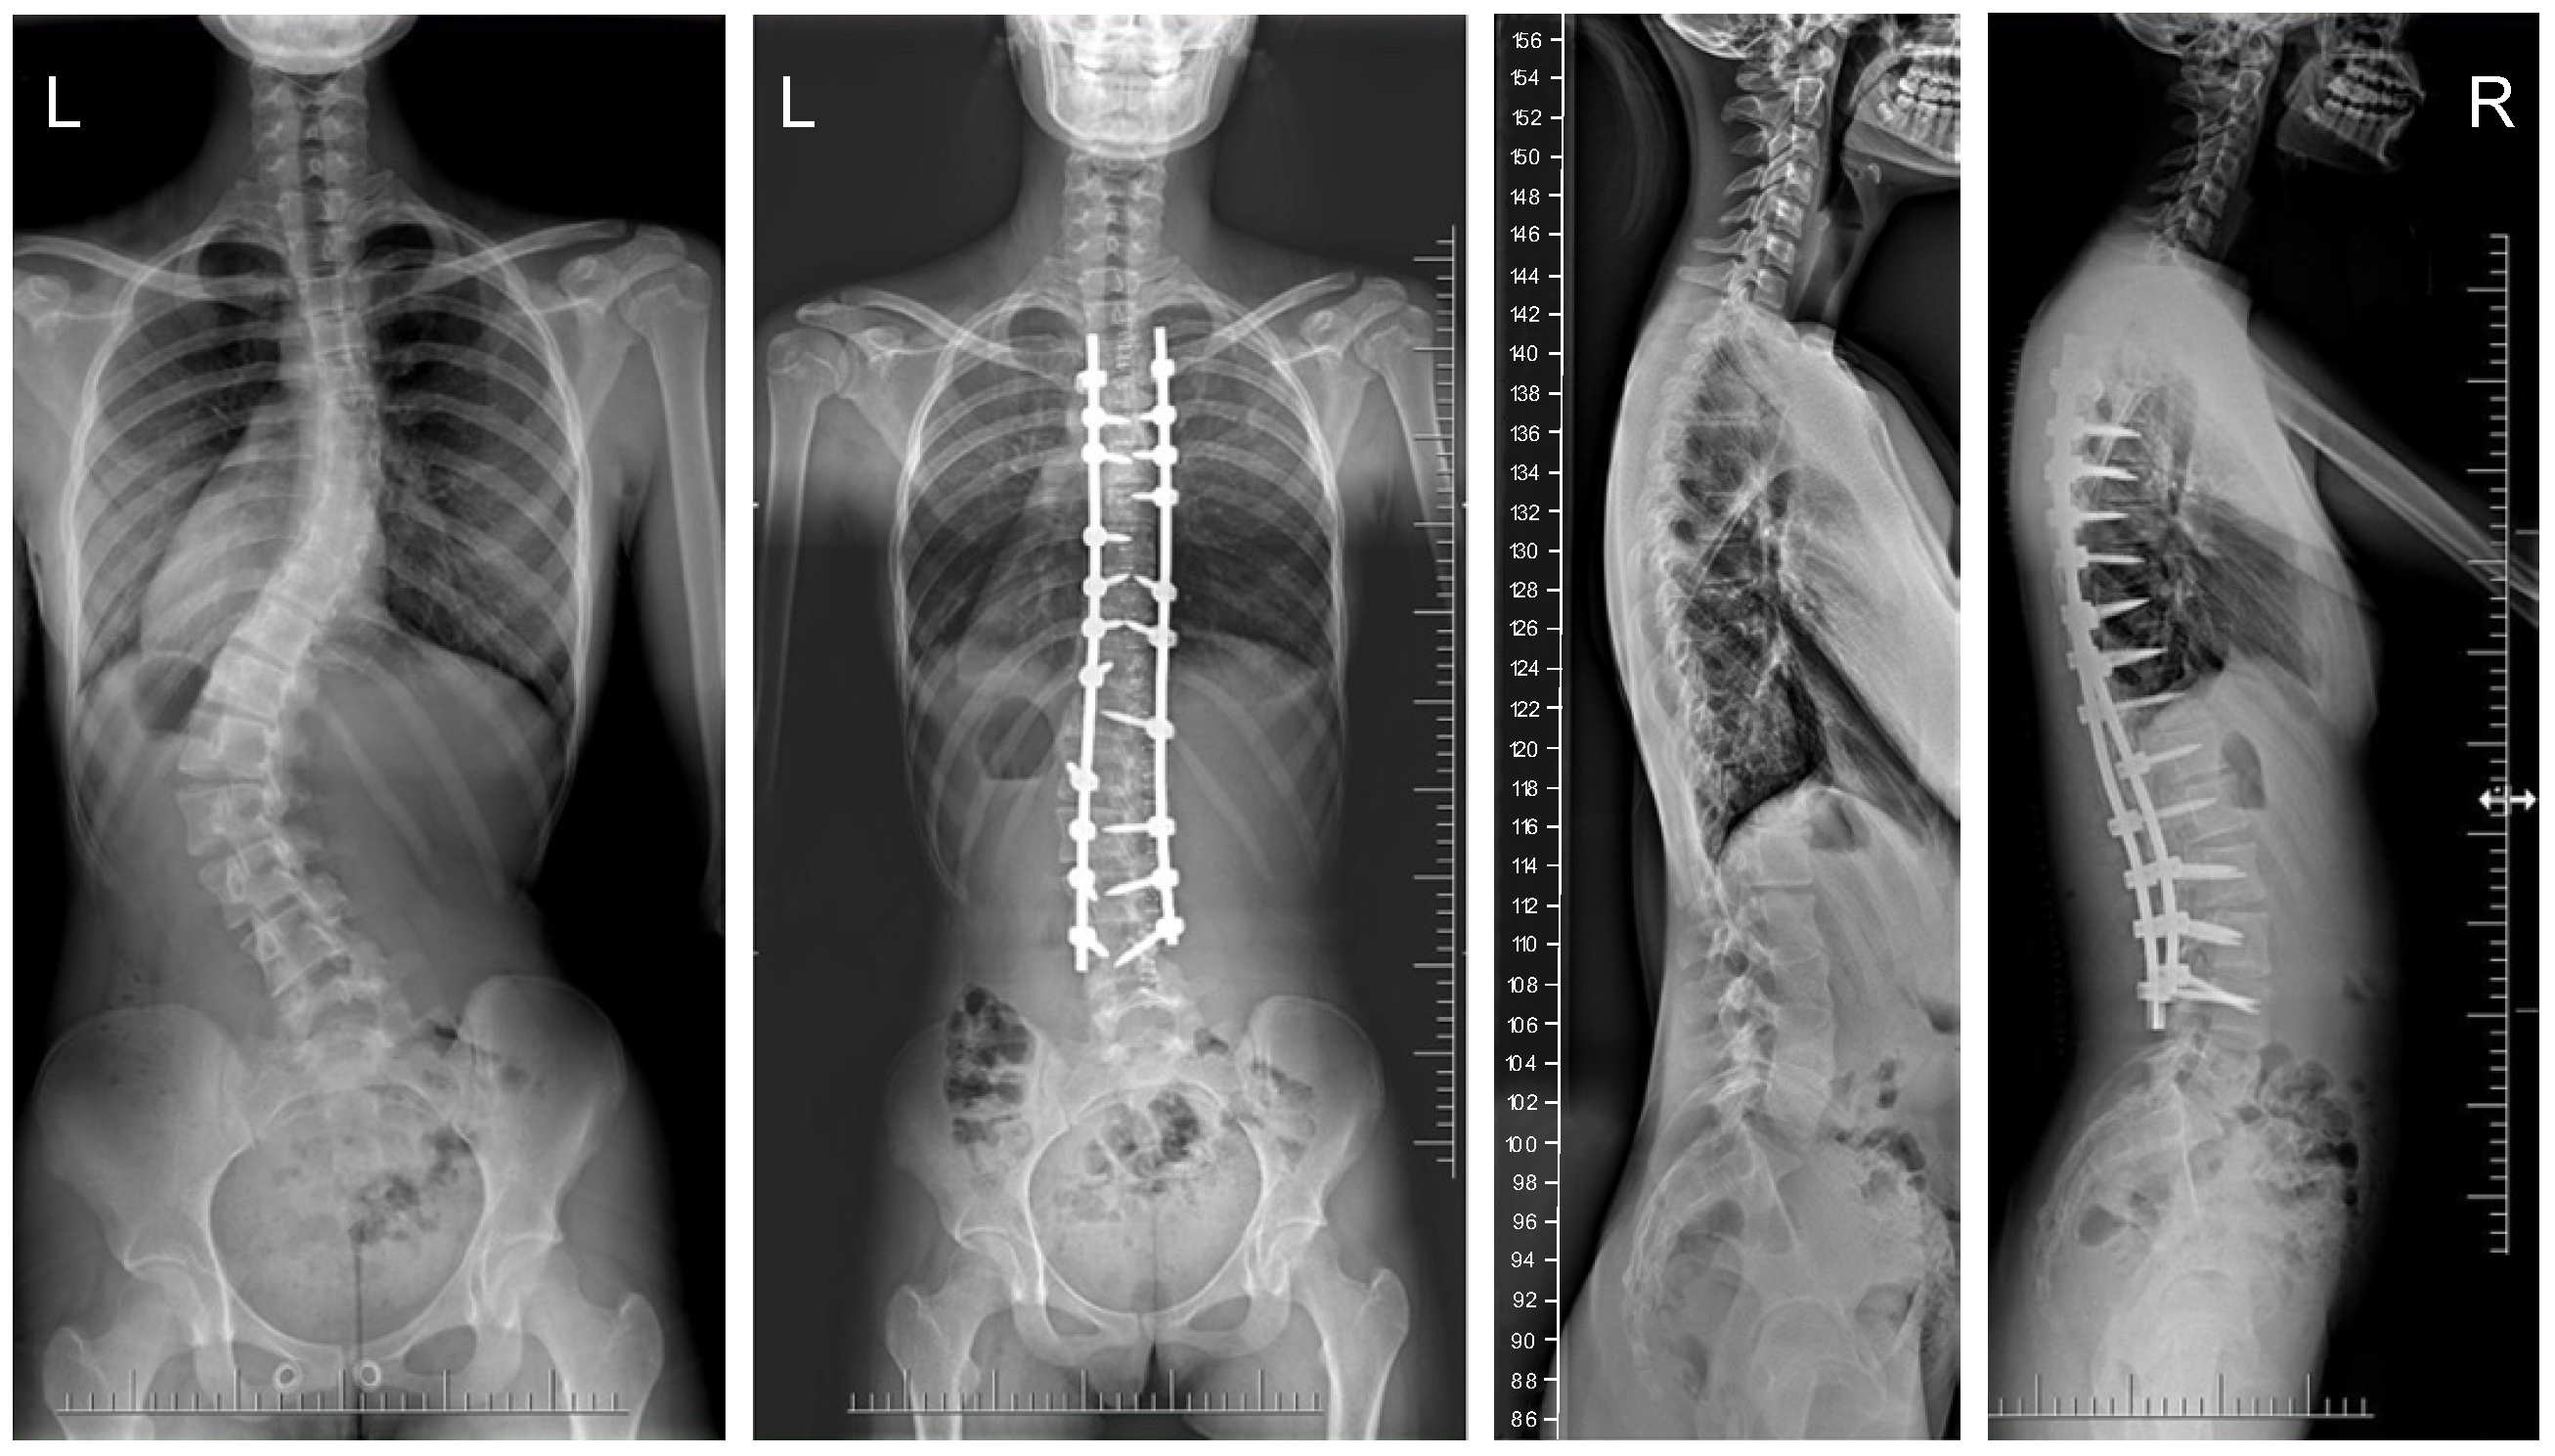

3.1. Clinical Characteristics and Radiographic Outcomes

| Preop major Cobb, degrees | 57.6 (11.9) | 62.5 (12.1) | 0.949 |

| Postop major Cobb | 19.8 (10.2) | 16.6 (8.2) | 0.001 |

| Final follow-up Cobb angle | 21.3 (9.2) | 17.1 (7.2) | 0.001 |

| % Cobb correction, postoperative | 69.8 (12.8) | 74.5 (11.2) | 0.001 |

| % Correction (FFU) | 61% (15) | 68% (14) | 0.001 |

| Flexibility rate | 35% (11) | 33% (8) | 0.382 |

| Ponte osteotomy levels (n) | 5.8 (2.2) | 5.6 (2.5) | 0.978 |

| Preop kyphosis T5–T12 | 25.1 (15.5) | 26.9 (15.8) | 0.779 |

| Postop kyphosis T5–T12 | 24.8 (8.8) | 23.5 (10.8) | 0.012 |

| Final follow-up TK T5–T12 | 25.2 (9.8) | 21.9 (10.2) | 0.001 |

| Apical vertebral translation at final follow-up, mm | 24 (5.8) | 22 (4.8) | 0.001 |

| Final follow-up sagittal balance, mm | 36.6 (22.6) | 27.6 (21.4) | 0.001 |